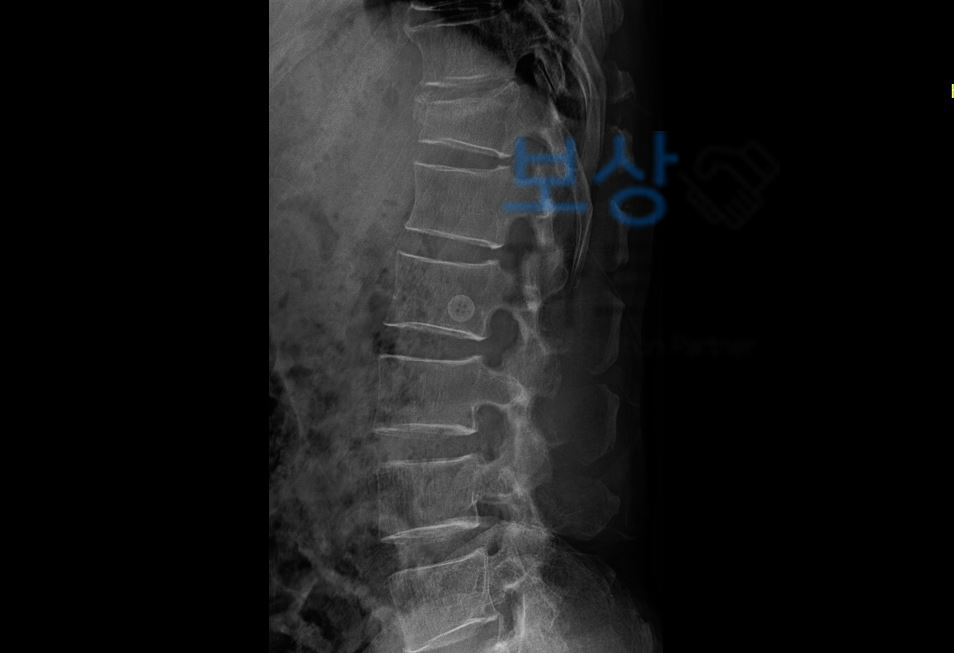

안녕하세요. 보상파트너입니다. 실제 문의들어온 사례 중 일산 거주하시는 심@@님은 교통사고를 당하게 되었는데요, 흉추압박골절 척추 장해 기준 T3번 T4번 T5번 T6번 T7번 금간 허리

심@@님은 병원에 내원하여 CT 및 Mri 촬영을 하셨고 척추의 다발성 압박골절 진단 받게 되었습니다.

흉추 3번부터 7번까지 척추에 금이가서 TLSO 허리보조기 착용해야 했는데요, 교통사고든, 일상생활 사고이든 척추 골절의 경우 충분한 치료에 더해 장해 보상 꼼꼼히 알아보셔야 하는데요, 교통사고인 경우에도 합의금 산정시 장해 평가 및 보상이 합의금에 큰 금액을 차지하고 일상생활 사고인 경우에도 개인적으로 가입한 보험에서 실비, 골절진단비, 입원비 말고도 후유장해 보상을 받을 수 있습니다.